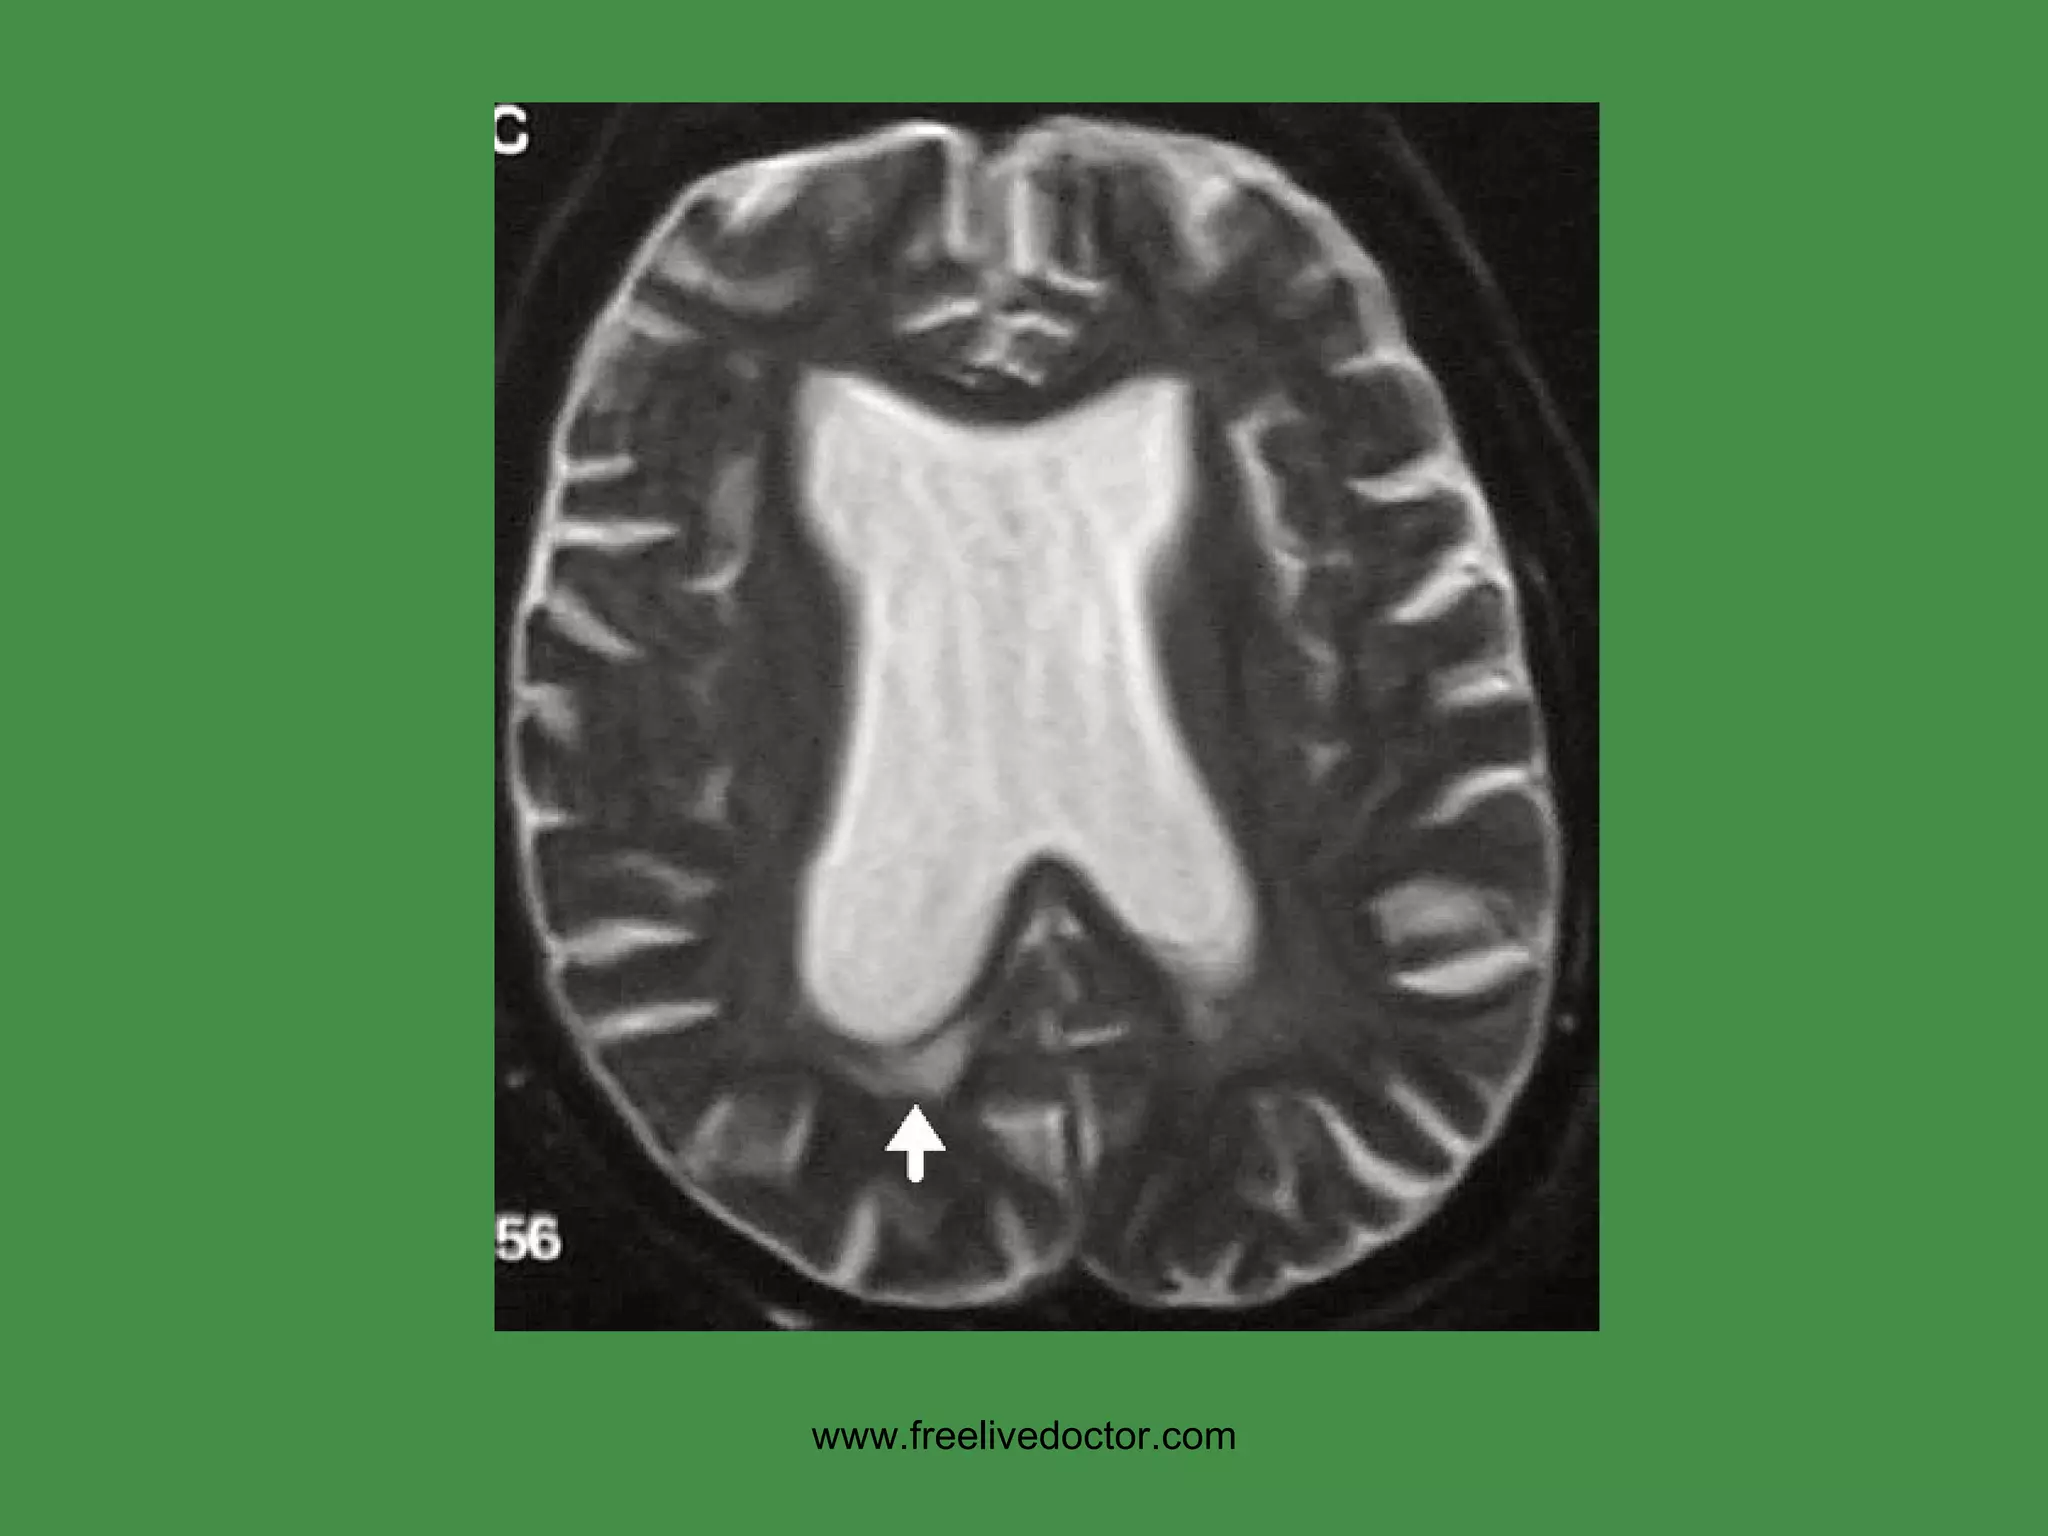

HUNTINGTON DISEASE Classical familial, genetic disease Progressive motor loss and dementia “ chorea”, i.e. “jerky” movements Progressive, fatal Atrophy of basal ganglia, i.e., corpus striatum Cortical (basal ganglia) atrophy Ventricular enlargement www.freelivedoctor.com

• #31 Hydrocephalus also showing cerebral edema, CT or MRI? Ans: CT Why? Ans: Bone is always very dense on CT, and water is always intense on T2 weighted MRI

• #32 Hydrocephalus, dilated ventricles